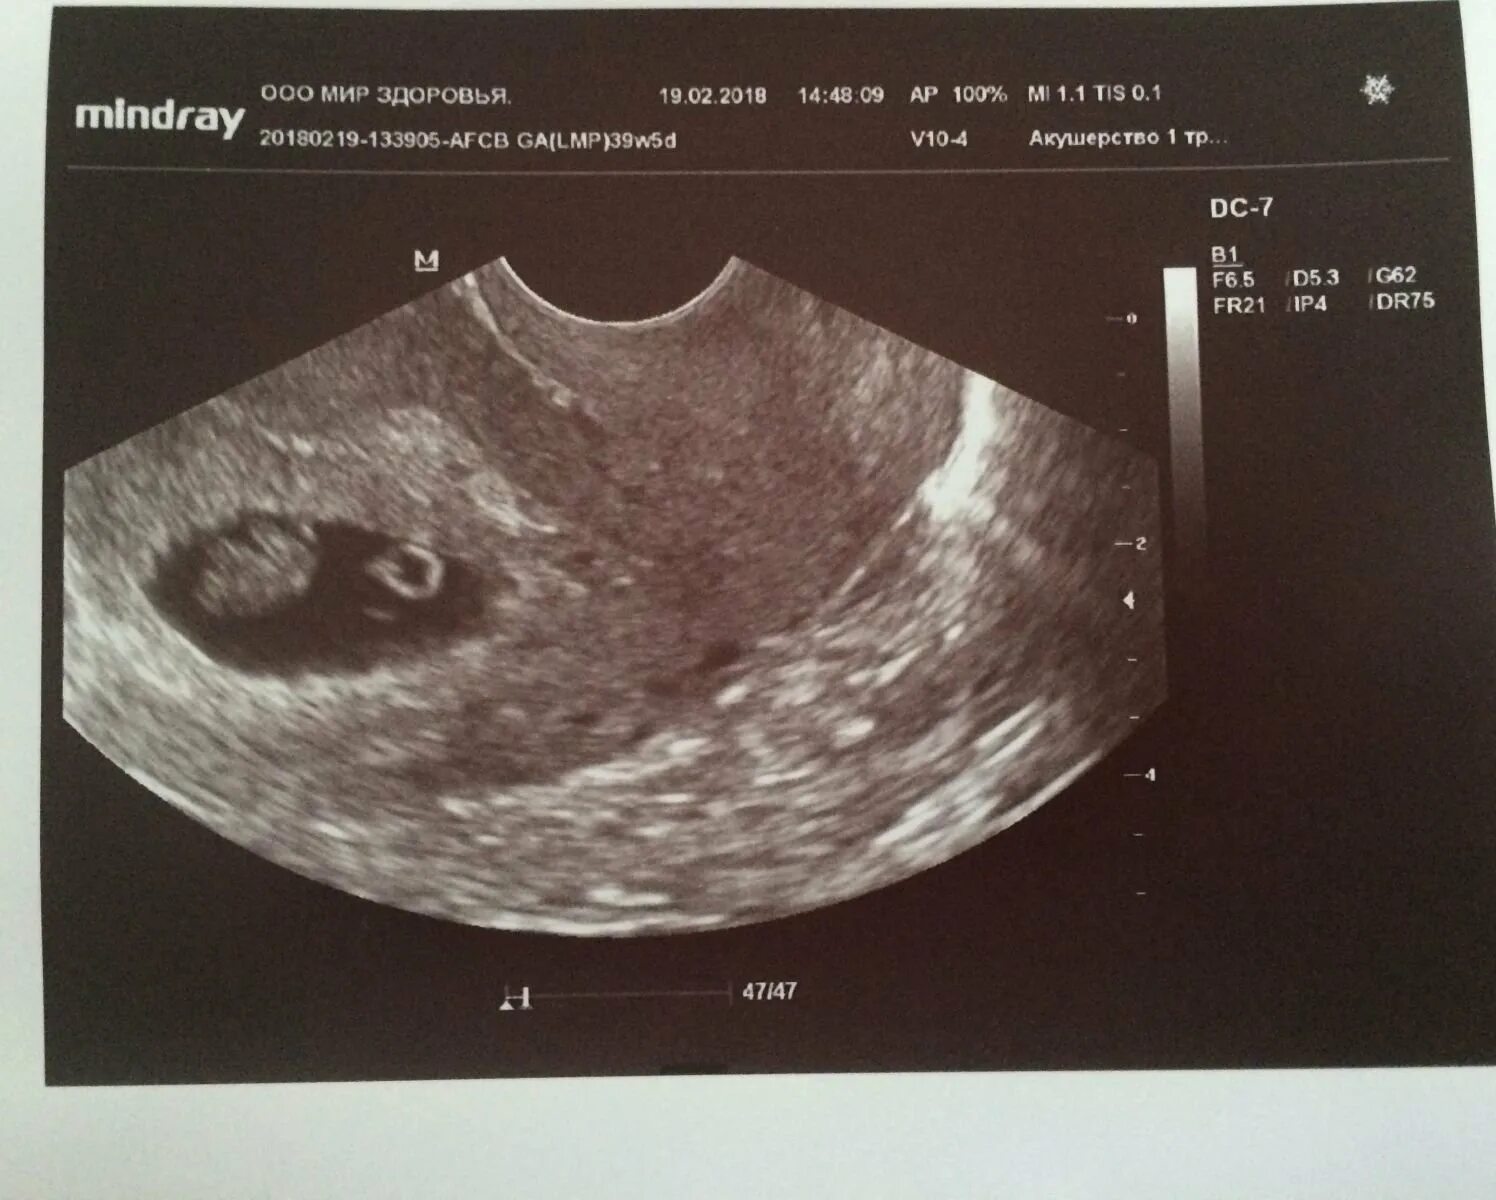

Плодное яйцо и эмбрион форум